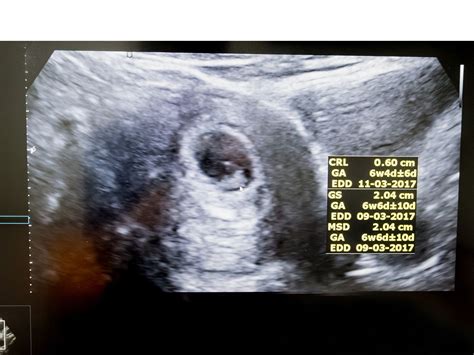

• Gestational Sac: The presence of a gestational sac confirms the pregnancy. It appears as a small, fluid-filled structure within the uterus.

• Yolk Sac: By week 6, a yolk sac may be visible. This structure provides early nutrition to the embryo and is a positive sign of a healthy pregnancy.

• Fetal Pole: The fetal pole is the earliest visible structure of the embryo. It appears as a small, curved line within the gestational sac.

• Fetal Heartbeat: A fetal heartbeat may be detectable by week 6, although it is more commonly seen by week 7. The heartbeat appears as a flickering motion on the ultrasound screen.

• Assessment of Gestational Age: The ultrasound helps determine the gestational age of the fetus, which is essential for monitoring growth and development throughout the pregnancy.